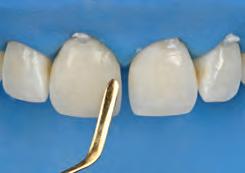

After developing the simulated mock-up, a 3D-printed resin model was created using CAD software (Fig 4a), and a clear PVS matrix (Exaclear, GC America) was fabricated to replicate the printed diagnostic wax-up using a nonperforated tray (Fig

4b). This matrix was used to create an intraoral motivational mock-up with bis-acryl composite (Luxatemp Ultra, DMG). This additive mock-up provides the interdisciplinary team with an intraoral translation for evaluation (Fig 5). Upon evaluation of the digital smile frame and the clinical translation, it was determined that multiple esthetic and restorative requirements were necessary for an optimal biologic framework, and the interdisciplinary team determined the best sequence for these procedures. The patient was presented with the interdisciplinary treatment possibilities that included restoring the maxillary anterior teeth and premolars with a minimally

invasive preparationless procedure or with less conservative veneer preparations. The restorative materials discussed included injectable resin composites and ceramic (ie, feldspathic, pressable, machinable). For an optimal biologic framework and health, it was determined that connective tissue grafting would be necessary for treatment of the recessiontype defects on the maxillary left central and lateral incisors, canine, and premolars. The patient opted for the conservative preparationless composite veneers using the injectable resin technique followed by a connective tissue surgical procedure using the tunneling technique.